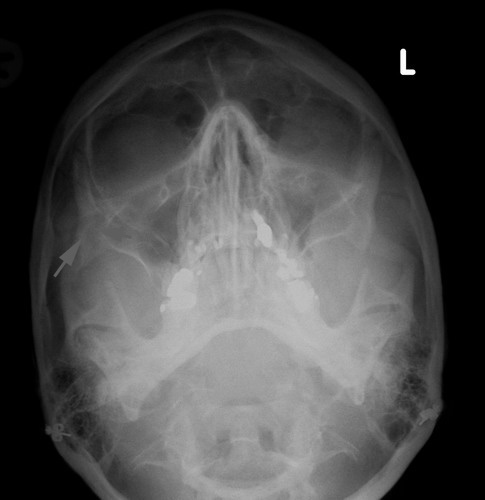

X-ray paranasal sinuses water's view will demonstrate fracture of zygoma.

X-ray paranasal sinuses showing fracture of arch of zygoma